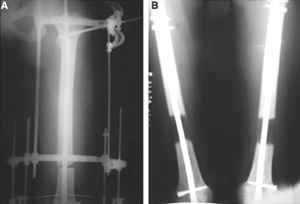

После заживления раны на левом бедре. Выполнить открытую реподицию и синтез пластиной для дистального бедра. Пластину в проксимальном направлении зафиксировать монокортикально.

А затем выпонить остеотомию бедра в верхней трети.

И тракцию бедра на стержне. Типа (СМ картинки).

После выращивания регенерата стержень блокировать.